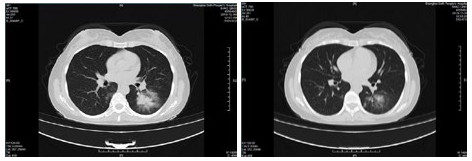

| 图 1 病例1,男性,65岁,沪籍,否认武汉流行病学接触史,发病前2周内每天有大型医院陪护史及疲劳史,既往体健,发热1 d入院,体温38.5℃,无咳嗽症状,无鼻塞,流涕,血白细胞总数及淋巴计数正常,甲乙型流感病毒筛查阴性,新型冠状病毒核酸检测阳性。肺部CT提示双肺多发磨玻璃结节,病灶贴近胸膜,局部小叶间隔增厚,炎症沿支气管血管走向分布,散在小结节影及纤维条索影 Fig 1 Case 1, male, 65 years old, born in Shanghai, denied the history of epidemic exposure of Wuhan. He had a history of accompanying in hospital every day and fatigue in the first two weeks before the onset of the disease. He was hospitalized one day after the onset of fever, with a body temperature of 38.5 ℃, no cough, no nasal obstruction and runny nose, normal WBC and lymph count, negative influenza A and B virus screening, and positive novel coronavirus nucleic acid test. Lung CT showed multiple ground glass nodules in both lungs. The focus was close to pleura, the interlobular septum was thickened, the inflammation distributed along the direction of bronchi and blood vessels, scattered in small nodule shadow and fibrous cord shadow |